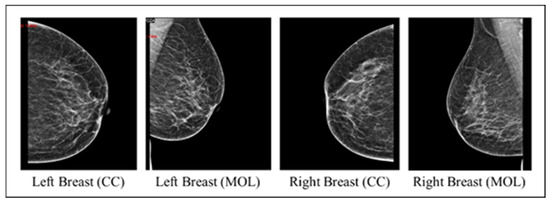

3.1.2. Images Dataset

- Checking that each record includes MLO and CC views for both breasts.

- Image cleaning: patient information and radiologist comments on mammograms were deleted manually using paint tools and Photoshop to preserve image quality.

- Image resizing: The original mammograms’ dimensions vary due to sources and devices. Therefore, Photoshop was used to resize all mammograms into 1800 × 1800.

- Data augmentation: The dataset initially consisted of 100 records from BI-RADS-1, 100 from BI-RADS-2, and only 56 from BI-RADS-5, creating an imbalance among these classes. To address this, random rotation and flipping were applied to BI-RADS-5 mammograms for data augmentation, increasing its records to 100. For the statistical data, slight random alterations were introduced to preserve feature integrity while balancing the classes. Figure 3 provides an overview of the preprocessing steps for the images.

- Uncleaned images: the model processes images containing text, with four mammograms for each patient, covering two views per breast side.

- Cleaned images: the same model is then applied to images devoid of text, also featuring four mammograms per patient and two views per breast side.

- The outperforming scenario between the uncleaned and cleaned images is rerun using only two images from the two views of the affected breast side.